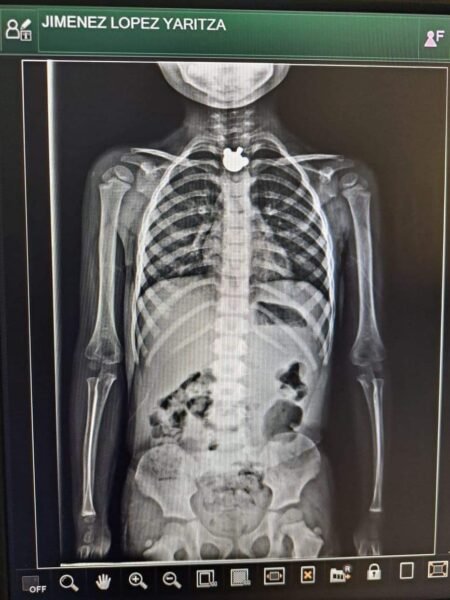

Una niña de Ocosingo, Chíapas, se encuentra grave de salud luego que por accidente se tragara una pieza de metal, fue trasladada a un hospital de San Cristóbal de Las Casas, donde los médicos hicieron todo lo posible por extraerle el objeto pero no fue posible sacarlo por la boca.

La niña de nombre Yaritza Jiménez López, se encuentra grave de salud y los familiares han solicitado el apoyo económico de la ciudadanía, cualquier donativo es recibido en la tarjeta bancaria de BanCoppel 4169160836206616 a nombre de Edith Sanchez.